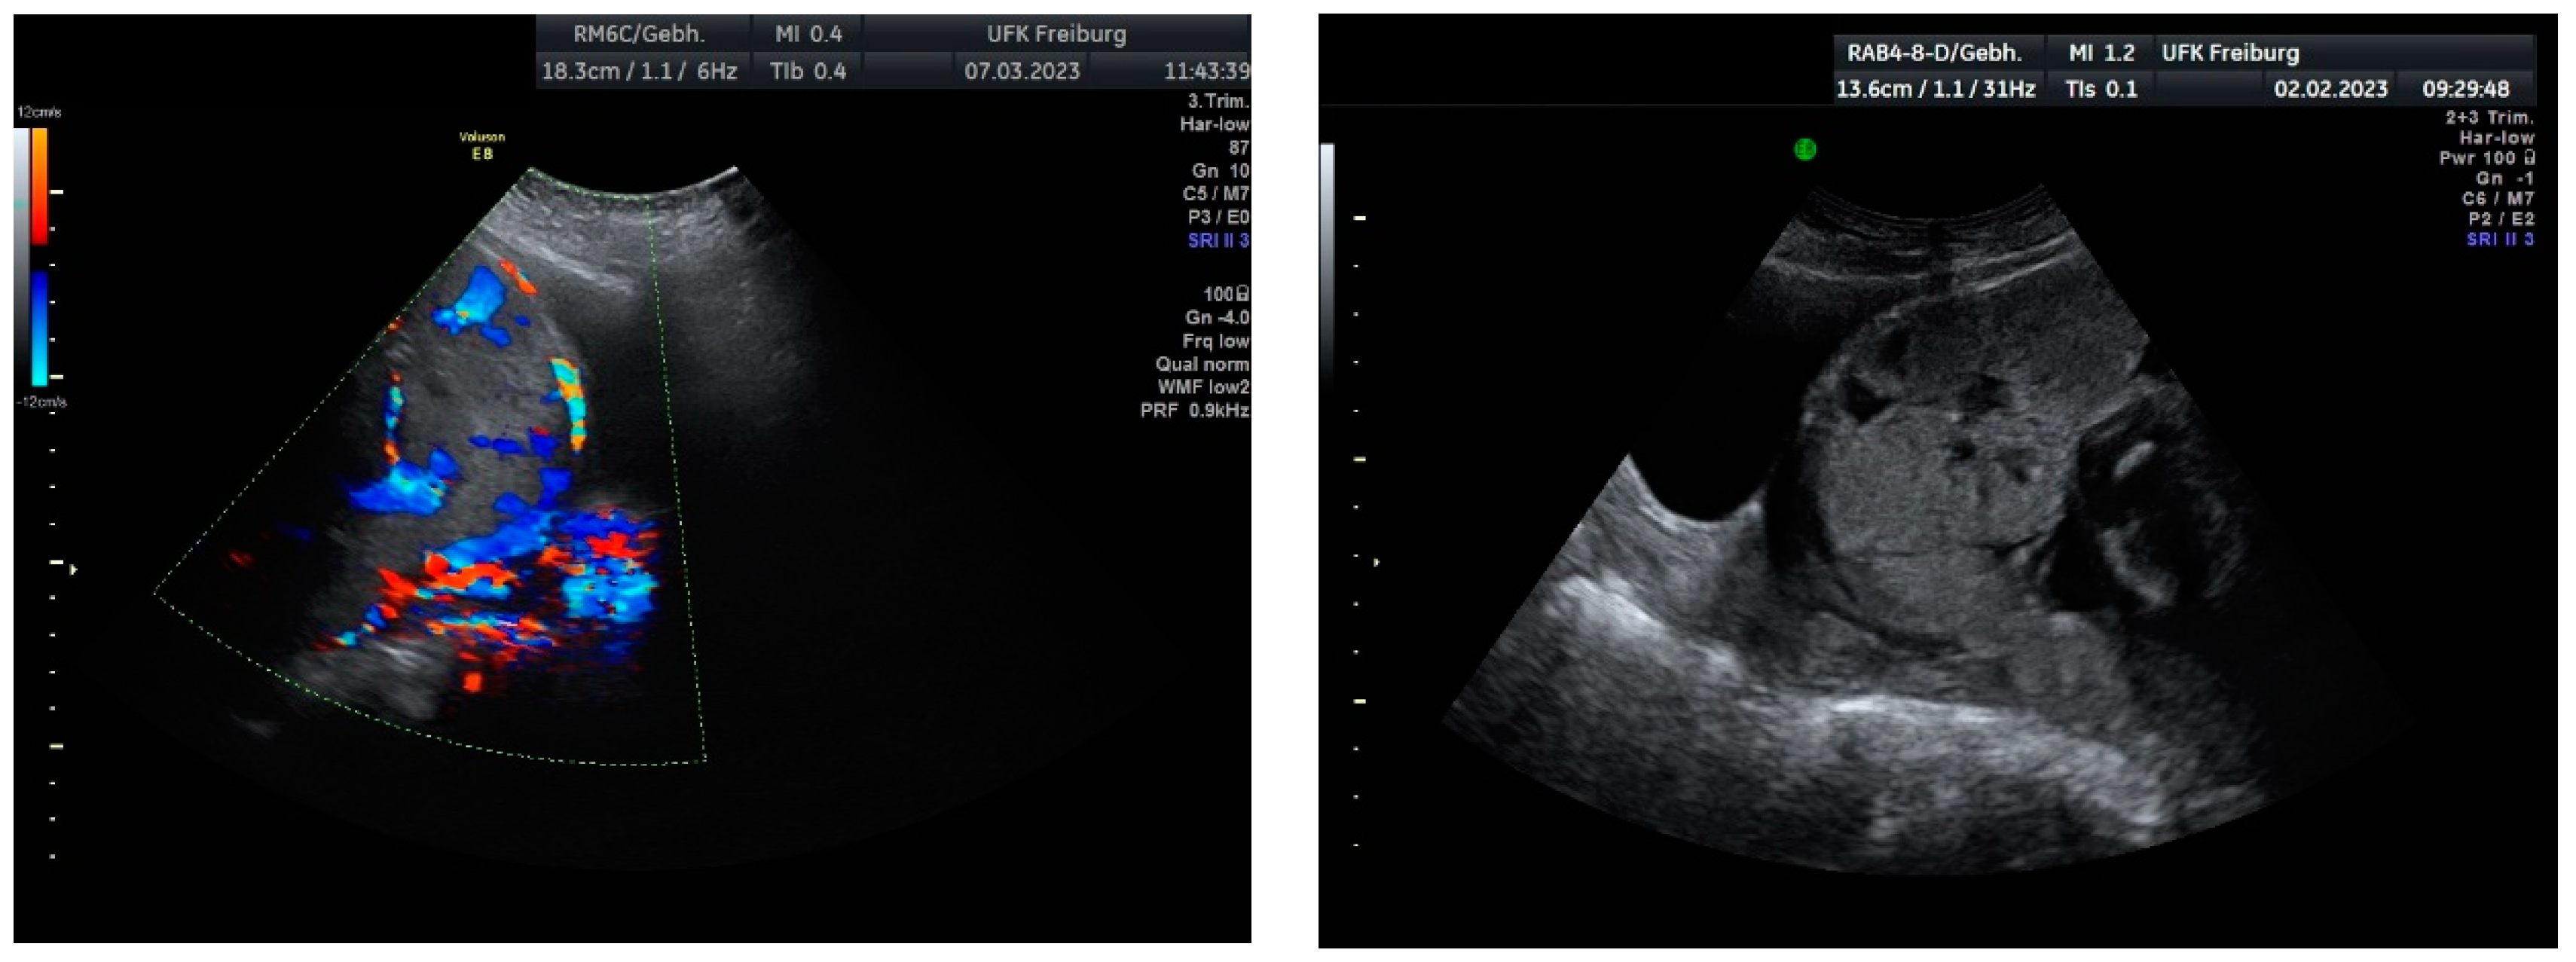

Sonographic findings (Figure 13):

Figure 13.

According to the standardized description of the European Working Group on Abnormally Invasive Placenta for ultrasound anomalies, the following anomalies may be seen: Loss of the “clear zone”—partially more in the middle (N/3):

- Abnormal placental lacunae;

- No interruption of the echoic bladder wall Myometrial thinning;

- No protrusion of the placenta into the bladder wall;

- No uterovesical hypervascularization;

- Subplacental hypervascularization.